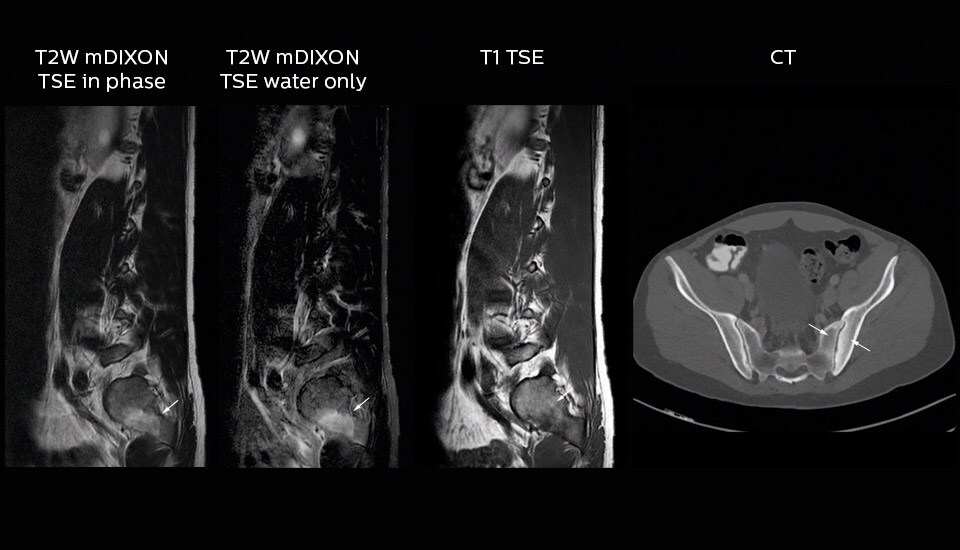

“In our lumbar spine MRI, the value of mDIXON TSE is so obvious. Normally we perform T1 and T2 scans in sagittal and transverse orientation.It used to take too much time to add a sagittal T2 with good fat suppression.But now, using mDIXON TSE, we get the sagittal T2 fat suppressed images ‘for free’, that is: without adding time.”   “Diagnostically that is a great benefit. I sometimes see abnormalities in the fat suppressed sagittal T2 that would be quite challenging to notice in the T2 without fat suppression. There have been several diagnoses that I could make easier because of our exam setup with mDIXON TSE, such as sacrum insufficiency fractures and sacroileitis; these were more challenging with our previous exam setup.”